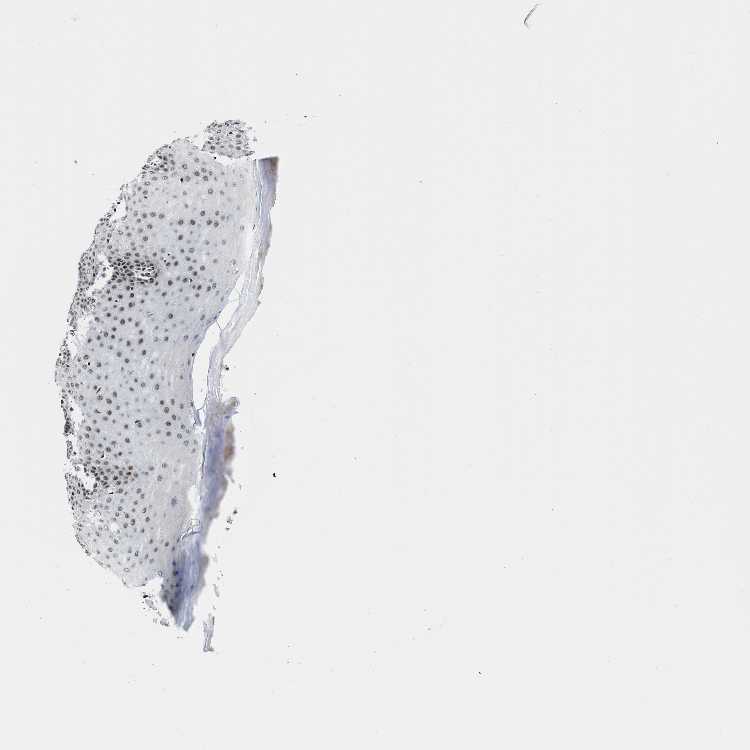

CERVIX - Antibody stainingi

Antibody staining in the annotated cell types in the current human tissue is reported as not detected, low, medium, or high, based on conventional immunohistochemistry profiling in selected tissues. This score is based on the combination of the staining intensity and fraction of stained cells.

Each image is clickable and will lead to virtual microscopy that enables deeper exploration of all samples and also displays staining intensity scores, fraction scores and subcellular localization as well as patient and tissue information for each sample.

Antibody HPA016610

Squamous epithelial cells High